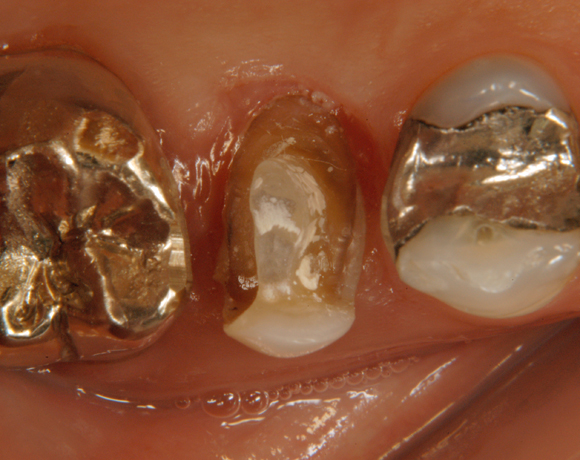

Ein Projekt aus dem Jahr 2003